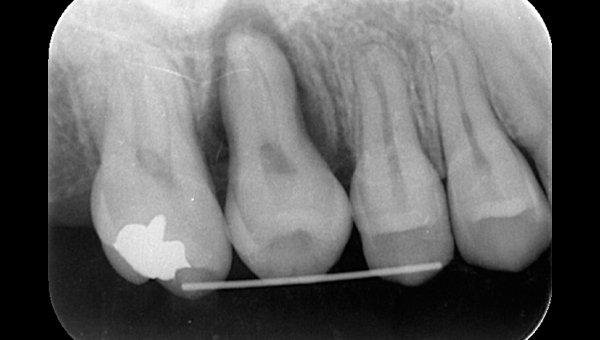

2021.4.3 定期検診時

この時はまだ症状がなかった

しかし歯は縦に割れており、いつ痛みが出てもおかしくないような状態であることは説明していた。

2022.1.15 根尖性歯周炎の急性化

疼痛ありで急患来院。

前々から爆弾抱えているような物で、何かあったら抜歯と伝えていた部位。以前よりクラウンマージン下で歯根縦破折であったが、症状なしで経過観察をおこなっていた。